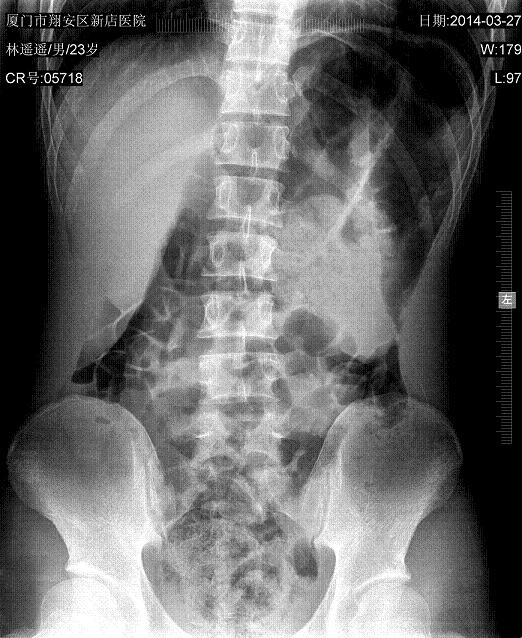

腹痛,无腹肌紧张,看看有什么事没有